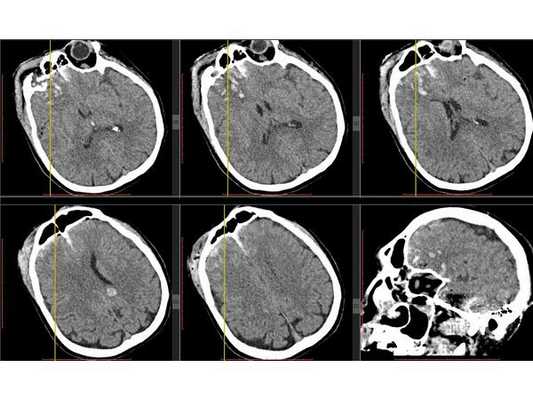

КТ головного мозга в первые сутки: выявлен линейный перелом лобной кости, переходящий на основание передней черепной ямки, и очаги ушиба полюсных отделов правой височной и лобной долей головного мозга (II вид по Корниенко), травматическое субарахноидальное кровоизлияние. Также выявлен двусторонний перелом нижней челюсти. КТ головного мозга на вторые сутки: выявлена трансформация очага ушиба правой лобной доли во внутримозговую гематому (агрессивный очаг ушиба головного мозга).

КТ головного мозга на вторые сутки: отсроченное формирование внутримозговой гематомы в правой лобной доле